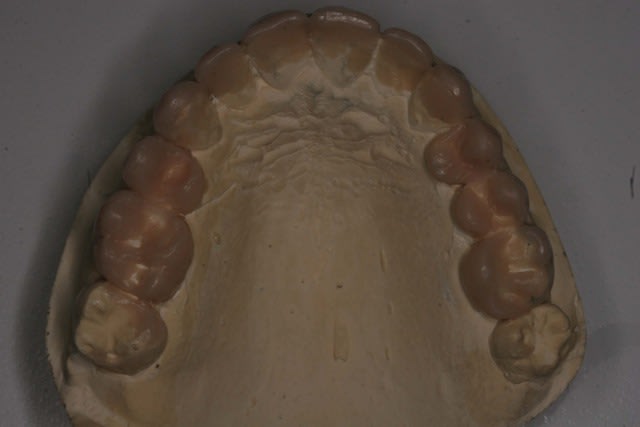

Voila la suite pour le maxillaire, le wax est fait sur arti en fonction de l'OIM obtenue après ortho. seule la 27 restera intacte.

Préparation des molaires pour permettre des RTE sous digue à travers les provisoires, retrait des anciennes couronnes et ancrages sur les 12, 15 et 25 endo satisfaisantes (couronnes ayant plus de 30 ans pour certaines!!!.

Tailles parallèles pour zircone 13 à 23 seront solidarisées pour éviter une migration post ortho.

Gingivectomie légère à la fraise à biseau pour harmoniser les collets, mais l'ortho a permis d'énormément faciliter ce travail.